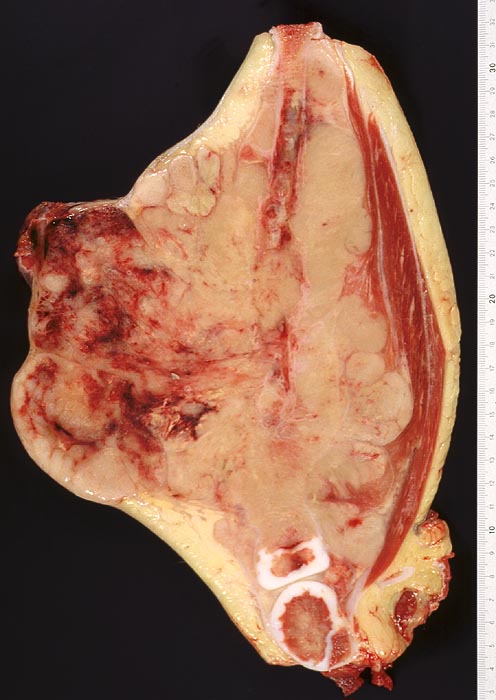

Die Tumoren sind makroskopisch grauweiss und wachsen destruktiv und infiltrativ. Nekrosen und Einblutungen sind häufig. Histologisch lassen sich solide Rasen monomorpher, kleiner, rundlicher Tumorzellen mit dichtem Chromatin und wenig Zytoplasma nachweisen (sog. small-blue-round cells). Metastasen treten vor allem in der Lunge und in anderen Skelettabschnitten auf. Die Differentialdiagnose klein-blau- und rundzelliger Tumoren im Kindesalter ist breit. Kleinzellige Osteosarkome, Neuroblastome, Lymphome und mesenchymale Chondrosarkome können ein histologisch ähnliches Bild zeigen, speziell in kleinen Biopsien, und müssen mit Hilfe von (molekularen) Zusatzuntersuchungen und unter Einbezug klinischer und radiologischer Befunde voneinander abgegrenzt werden.

Meist entstehen Ewing Sarkome primär im Knochen. Es kommen aber auch extraskelettale Formen vor. Prinzipiell können alle Skelettabschnitte betroffen sein. Bevorzugt befallen sind aber die langen Röhrenknochen (diaphysär), das Stammskelett, der Schädel, die Rippen und der Beckengürtel. Extraskelettale Ewing Sarkome liegen am häufigsten paravertebral oder in der Brustwand, seltener in anderen Weichteilen.